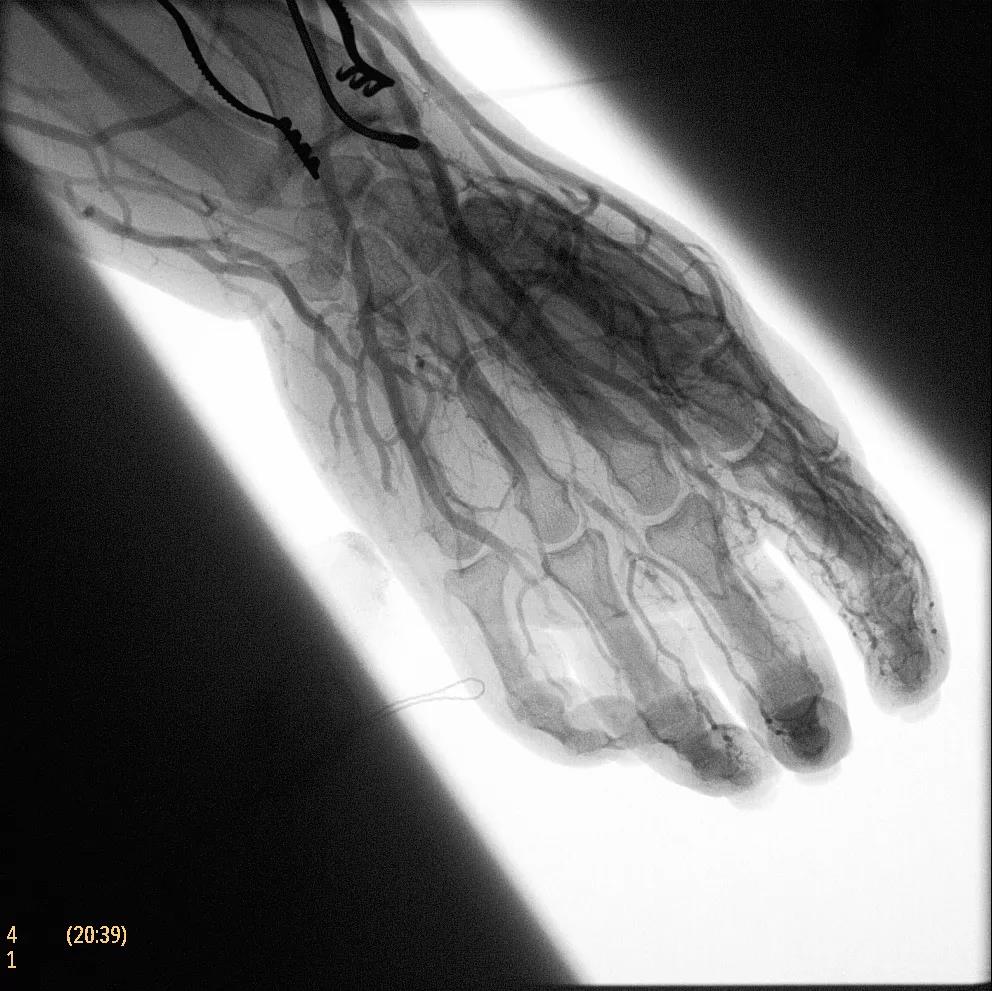

飛利浦于2019年2月18日宣布推出帶扁平探測器的移動式C臂Zenition 70。Zenition 70使用飛利浦第四代Flat Detector系統(tǒng),具有卓越的成像清晰度和靈活性,可執(zhí)行各種情況。

據(jù)器械之家了解到,移動式C型臂是X射線系統(tǒng),可帶入手術(shù)室(OR),在整形外科、創(chuàng)傷和血管手術(shù)等各種手術(shù)過程中提供實時圖像引導(dǎo)。Zenition70使醫(yī)院能夠最大限度地提高OR性能,增強臨床能力并為員工提供高質(zhì)量的用戶體驗。

( Zenition 70匯集了圖像捕獲,圖像處理,易用性和多功能性方面的創(chuàng)新。)

在快速增長的圖像引導(dǎo)微創(chuàng)手術(shù)領(lǐng)域 ,手術(shù)干預(yù)的范圍和復(fù)雜性在繼續(xù)增加,需要治療的患者數(shù)量也在增加。為了以更低的成本治療更多的患者,醫(yī)院需要具有不同能力的多功能C臂組,以便容易地適應(yīng)不同類型的手術(shù)和不同操作者的需要。Zenition 70易于在手術(shù)室之間移動,易于在患者周圍定位并且操作直觀。

飛利浦Zenition 70支持整個醫(yī)療保健機構(gòu)提高OR性能。平臺類似平板電腦的用戶界面和簡單的統(tǒng)一工作流程意味著一旦操作員學(xué)會在平臺上使用一個系統(tǒng),他們就可以輕松地操作它們。該系統(tǒng)可在任何介入或外科手術(shù)過程中快速直觀地拍攝傻瓜相機。Zenition的緊湊設(shè)計,位置記憶功能(僅適用于Zenition 70)和BodySmart軟件,即使在圖像增強器或平板探測器的邊緣也能捕捉快速一致的圖像,將C臂重新定位的需求減少45%。

( Zenition 70采用與Azurion平臺相同的圖像處理算法。

為了獲得清晰的高質(zhì)量圖像,Zenition 70 采用了與公司Azurion平臺相同的圖像處理算法,可提供患者解剖結(jié)構(gòu)的高清可視化和更大的可視區(qū)域。飛利浦的MetalSmart軟件等功能可確保圖像質(zhì)量,該軟件可自動調(diào)整圖像的對比度和亮度,以便在視野中存在金屬物體(如植入物)時提高圖像質(zhì)量 - 這一特性使Zenition 70在整形外科中特別有用。